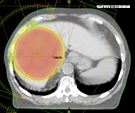

標題: 84歲嬤膽管癌指數破千!醫病共決採精準放療免挨刀

腫瘤

病灶

放射線

膽管癌